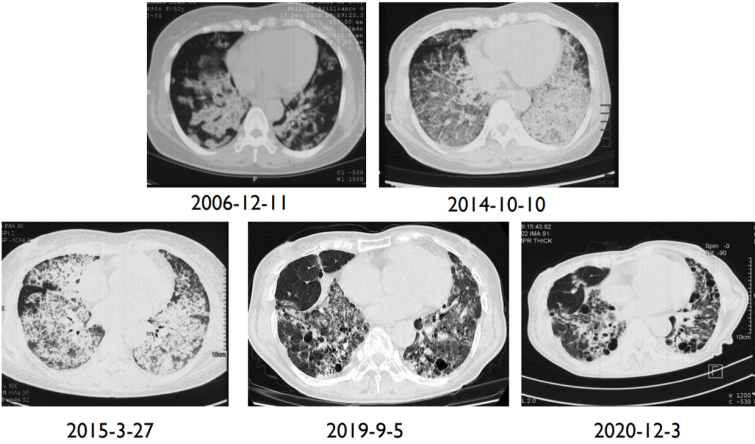

17年前(2006年底),患者体检时胸CT发现“双肺以肺门为中心呈蝶翼状分布的片状实变影,向外延伸,可见支气管充气征及肺间质改变”(图1),无发热、咳嗽、咳痰、呼吸困难、胸闷等不适。就诊于北京某三甲医院,行支气管镜检查(2006-12-21),镜下未见异常,于右肺中叶灌入生理盐水100 ml,回收40 ml,灌洗液外观乳白色浑浊,静置20 min可见沉淀;BALF(右肺中叶)细胞学:符合肺泡蛋白沉积症,PAS(+);左下肺基底段经支气管肺活检(TBLB)病理:少许支气管黏膜、软骨及肺组织,PAS(-)。综上考虑诊断“肺泡蛋白沉积症”,但因患者无明显临床症状,未进一步治疗,嘱其密切随访。

图片

1  患者2006年12月胸部CT

9年前(2014年),患者呼吸困难逐渐加重,不能爬山或剧烈活动,爬2层楼梯后自觉憋气,伴咳嗽、咳痰加重,晨起为著,无发热、咯血、胸痛。再次就诊于北京某三甲医院,动脉血气分析(2014-08-27,未吸氧):pH 7.41,PaCO2 35.5 mmHg,PaO2 49.1 mmHgSaO2 82.4%;胸部CT示:双肺野可见弥漫性斑片状高密度影,部分呈铺路石样改变(图2);肺功能示:限制性通气功能障碍伴弥散功能减低(表1)2014年9月22日行全麻下全肺灌洗术,双肺均灌洗生理盐水10000 ml,分别回收淘米水样灌洗液10300 ml(左肺)及10750 ml(右肺),术后呼吸困难症状好转不明显,鼻导管吸氧5 L/min时,指脉氧饱和度可维持95%左右。出院后规律门诊随访,呼吸困难症状未减轻,需氧疗,加用粒细胞-巨噬细胞集落刺激因子(GM-CSF)150 μg 2次/日(用1周、停1周)雾化吸入治疗数月,患者症状略改善。

2  患者2014年9月胸部CT

8年前(2015年3月),患者症状再次加重,停用GM-CSF吸入治疗寻求中医,就诊于北京某三甲中医院,开始服用中药汤剂(具体不详),起初疗效良好,自觉症状较前明显好转,可完全脱氧,安静不吸氧状态下指脉氧饱和度为95%,后效果逐渐减退。治疗期间胸部CT如图3所示。

3  患者2015年3月27日胸部CT

4年前(2019年4月),在北京某三甲中医院应用两次利妥昔单抗(500 mg),症状仍不见好转,患者病情再次恶化,活动后呼吸困难再次加重,活动耐力显著下降,安静不吸氧状态下指脉氧饱和度最低约为80%,需持续家庭氧疗,鼻导管吸氧3 L/min时,指脉氧饱和度可维持在95%。2019年9月5日胸部CT示:斑片实变影进展为蜂窝网格影,出现双肺纤维化及牵拉支扩改变(图4)2019年11月,患者于我院评估后考虑特发性肺泡蛋白沉积症(PAP),抗GM-CSF抗体19.4 μg/ml,建议肺移植。

4  患者2019年9月5日胸部CT

3年前(2020年12月),患者受凉后出现发热,Tmax 37.8℃,伴咳嗽、咳白痰增多,呼吸困难加重,呼吸频率最快可达40次/分左右,平地行走50米即喘憋明显,进食量下降,夜间休息极差,体重5年下降约20 kg;胸部CT如图5所示。为寻求肺移植手术行术前评估。

5  患者2020年12月3日胸部CT

6所示为患者从2006年发现肺部病变到2020年12月胸部CT的演变。

6  患者术前胸部CT演变